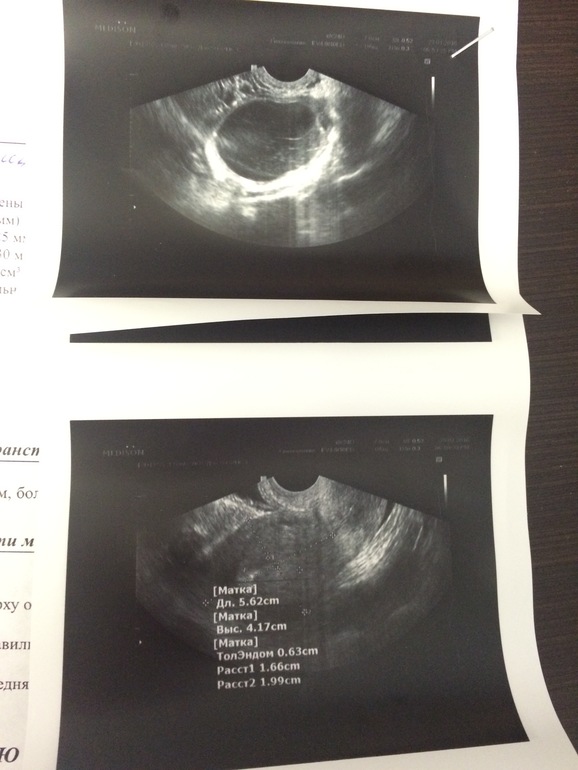

Я по гинегологии только рожала. А тут такое.... Мы почти делечили мужа. У него проблемы с гормонами,следствием чего стали другие проблемы... Куча денег,лечение,все дела... В феврале нам должны сказать,получилось ли. И вот в период овуляции стал колоть правый бок,такая пульсирующая точечная боль... Спустя неделю сексом стало заниматься больно. Прям во что-то упирается и копеец! Искры из глаз! Пошла на узи... Киста,блин! Правого яичника. Врач дала понять,что если помимо этого узи я буду у нее наблюдаться,то все скажет. А пока пусть со своим узи валю куда подальше подумать. Может воспаление,может гормональное,а может и все в порядке,выйдет с месячными...Я ревуууу... Так обидно. Киста 6*5*5 примерно... Я ее чувствую. Так плохо мне... Послезавтра 30 лет,то ли на больничны идти,то ли месячных дождаться,но вот секс точно отменяется--больно очень... И не знаю,куда податься(( лечить? Ждать?... Девочки,поскажите?...